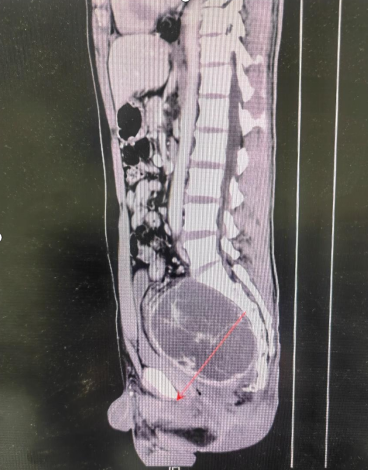

37岁的李先生近年来被反复出现的下腹坠胀、排尿困难等问题困扰,生活质量严重下降。经检查发现,其盆腔内存在一巨大占位性病变,进一步诊断明确为盆腔巨大肿瘤。肿瘤直径接近20厘米,几乎填满了整个盆腔,与直肠、膀胱、输尿管及重要血管神经关系密切。

面对这一复杂病例,医护团队迎难而上。为确保手术安全、提高治疗效果,科室启动了多学科诊疗(MDT)模式,联合放射科、泌尿外科、血管外科、麻醉科、手术室、输血科等多个科室专家进行深入讨论。团队通过高分辨率影像资料对肿瘤的形态、血供、与周围脏器的关系进行了三维重建与细致评估,制定了周密的手术方案和应急预案。同时,医护团队为患者进行了充分的肠道准备、备血等术前工作,为打赢这场“硬仗”做足了准备。